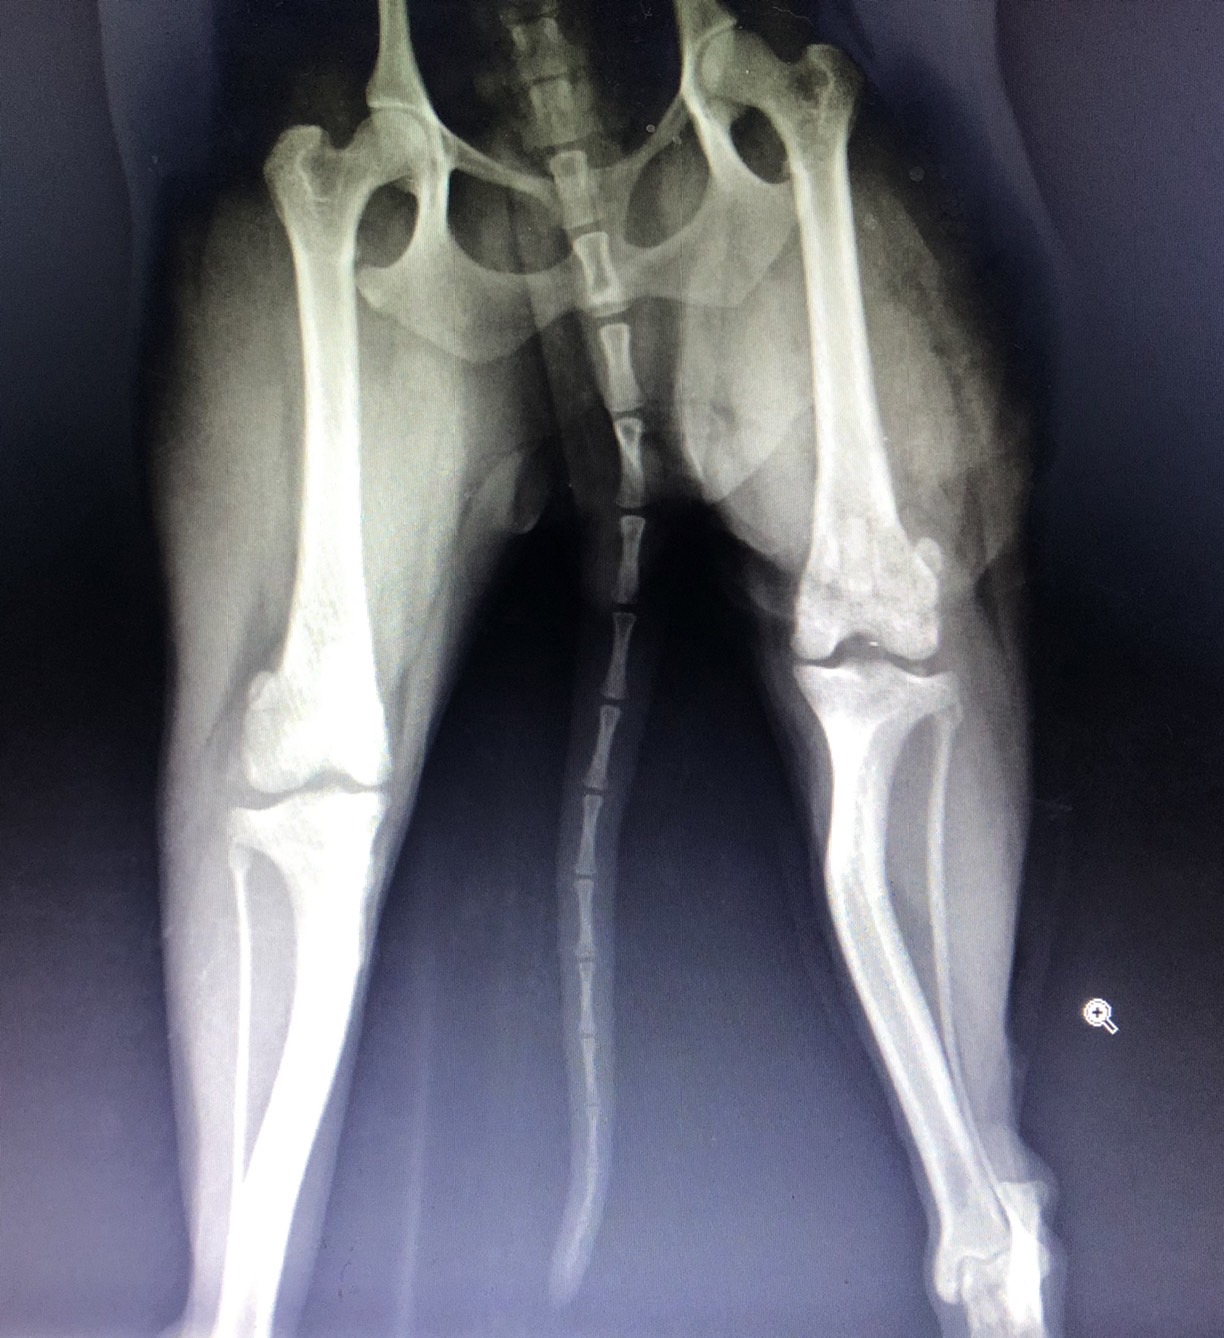

術前x光 左後肢膝蓋骨異位

經觸診搭配x光影像發現左後腳膝蓋骨異位2-3級,